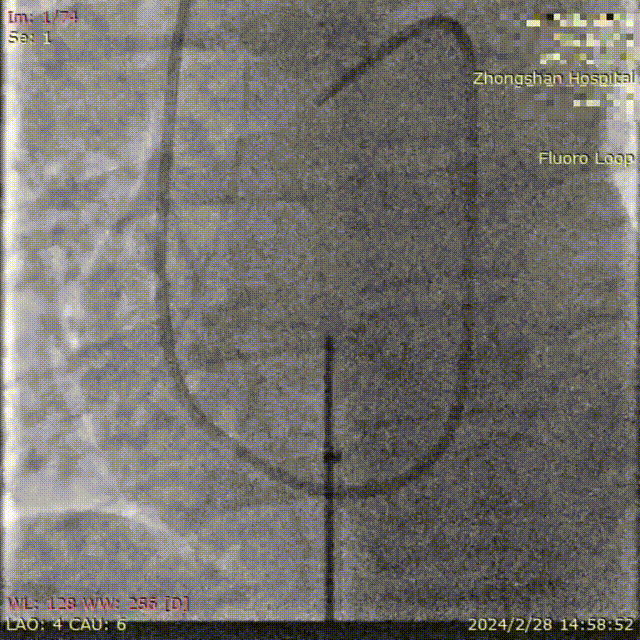

葛均波院士为患者植入FreeFlow经皮房间隔分流器,在DSA的监测下分流器左盘通过输送鞘管到达左心房并释放;回撤输送鞘管,释放分流器右盘;行牵拉试验,观察分流器形态、位置、左右心房分流情况;旋转输送钢缆将分流器完全释放;撤离输送钢缆、输送鞘管,手术圆满完成,分流器释放性能、输送系统操作性能均表现良好。复查心超/DSA,分流器位置、大小、形态合适,对周围结构无影响,清晰可见右向左分流。

释放分流器左盘